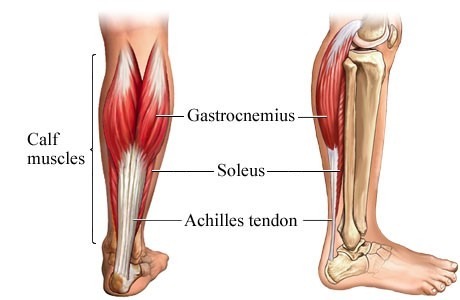

Anatomisk bilde av m.tricpes surae og akillessenen

Når man Googler akilles vil man som oftest møte en gresk helt og en stor kriger, nemlig Akilles fra gresk mytologi. I anatomisk forstand kan akillessenen også ses på som en helt med tanke på at musklene som danner akillessenen er de to viktigste musklene i fra skyvet under løp og gange. Under gange blir akillessenen utsatt for belasting tilsvarende 2-3 ganger kroppsvekten, mens ved løp kan den bli utsatt for belastning opptil 12,5 ganger kroppsvekten (Komi, Fukashiro, & Jarvinen, 1992).

Den vanligste akillessenerupturen (53%) oppstår under fra skyvet i hopp eller løp med kneet i full strekk (Gross & Nunley, 2016). En annen skademekanisme (17%) er en uventet bøy av ankelleddet med en umiddelbar kontraksjon av bakside leggmuskelen (Gross & Nunley, 2016). Enkelte pasienter kan fortelle om langvarig akillessenesmerter i forkant av rupturen, men som oftest oppstår skaden uten forvarsel. De aller fleste pasientene oppdager umiddelbart at noe galt og oppsøker selv helsepersonell. Det er viktig at helsepersonellet som undersøker pasienten har god kunnskap på feltet og ikke minst klinisk erfaring.

Da det er et sterkt samspill mellom musklene som danner akilles og de andre musklene i leggen bør helsepersonellet som utfører undersøkelsene bør ha erfaring med akillessenerupturer for å stille den riktige diagnosen. Ved LFI helse & trening har vi idrettsfysioterapeuter som har god kunnskap og erfaring med å stille diagnoser på akutte skader.